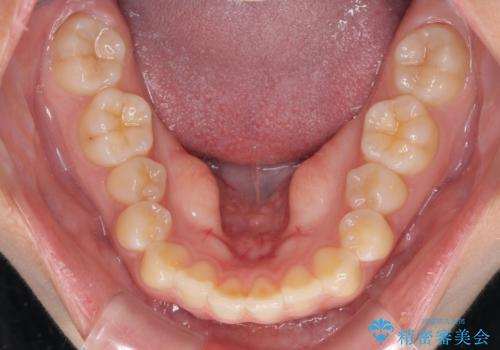

- 前歯の叢生を気にして来院された患者様です。

奥歯の咬み合わせを見ると、上顎が下顎に対して相対的に前方にあり、上下の前歯が接触していない状態でした。

咬み合わせを改善するためには、上顎臼歯を後方に移動させた咬み合わせにする必要があります。

インビザライン単体で改善することも可能ですが、咬合力が強く、単位で達成する可能性が低いと考えられたため、カリエール・ディスタライザーという補助装置を併用して、より確実性を上げることとしました。

奥歯の咬み合わせを改善しながら、並行してインビザラインで歯列を整えることとしました。